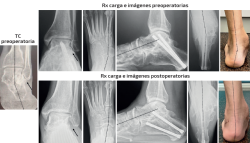

Caso 1 (Figura 4)

Se trata de una paciente mujer de 25 años afecta de dolor medial y sinus tarsi. Antecedente en adolescencia de esguinces laterales frecuentes. Diagnosticada previamente de forma errónea de microinestabilidad de tobillo. Evidencia de coalición ósea talocalcánea en pruebas de imagen y deformidad clínica y radiológica con predominio de abducto. Subtalar rígida. Tipo IIB de Myerson. Tratamiento: osteotomía de alargamiento de la columna externa con cuña de metal trabecular como único gesto quirúrgico. Seguimiento: 2 años. Capaz de caminar largas distancias sin dolor. Mejoría de la alineación clínica y en las radiografías dorsoplantar y de Saltzman. Sin cambios en las ángulos sagitales.